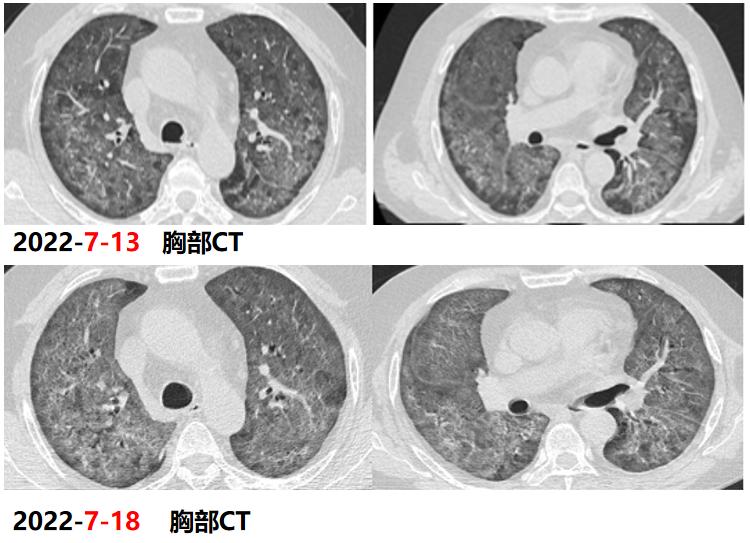

2022年7月17日:患者气喘较前明显好转,改口服SMZ;7月18日:复查胸部CT。患者仍有活动性气喘,暂续前治疗;7月20日:气喘明显加重,急查血气;7月22日:炎症指标上升,转ICU行气管插管+呼吸机辅助呼吸,CRRT。

2022年7月18日,患者胸部CT见双肺间质性炎症范围较前扩大,考虑PJP感染导致的间质性炎症持续渗出。

患者属重症PJP,给予静脉使用SMZ注射液病情一度好转,但因经济原因,改为口服SMZ治疗,后病情进展迅速。

2022年7月24日,BALF-mNGS检出耶氏肺孢子菌、肺炎克雷伯菌。肺炎克雷伯菌系院内感染。7月28日,多次复查血常规提示血小板进行性下降;8月8日:抗生素降阶梯;8月10日:气管插管2周,暂难脱机,需行气管切开,血小板低,输注血小板,择期行气切;8月13日:血小板进行性下降,感染消耗可能。血小板27X109/L、CRP89.2mg/L;8月16日:复查血常规示三系进行性下降,降钙素原升高15.6ng/ml,感染加重;8月17日:炎症指标较前明显升高,调整抗生素。血小板16X109/L、CRP272mg/L;8月18日:患者深昏迷,FIO2100%,血氧饱和度波动于60%-80%,去甲肾上腺维持血压,随时可能出现死亡风险,患者家属强烈要求出院,劝阻无效,予办理自动出院。血小板11X109/L、CRP326mg/L。

从该例病例,我们可以看到,PJP的早期诊断和治疗非常关键,及时早期使用SMZ的治疗对预后起着决定性的作用,对于重症PJP,建议尽早使用SMZ注射液,并序贯口服治疗。